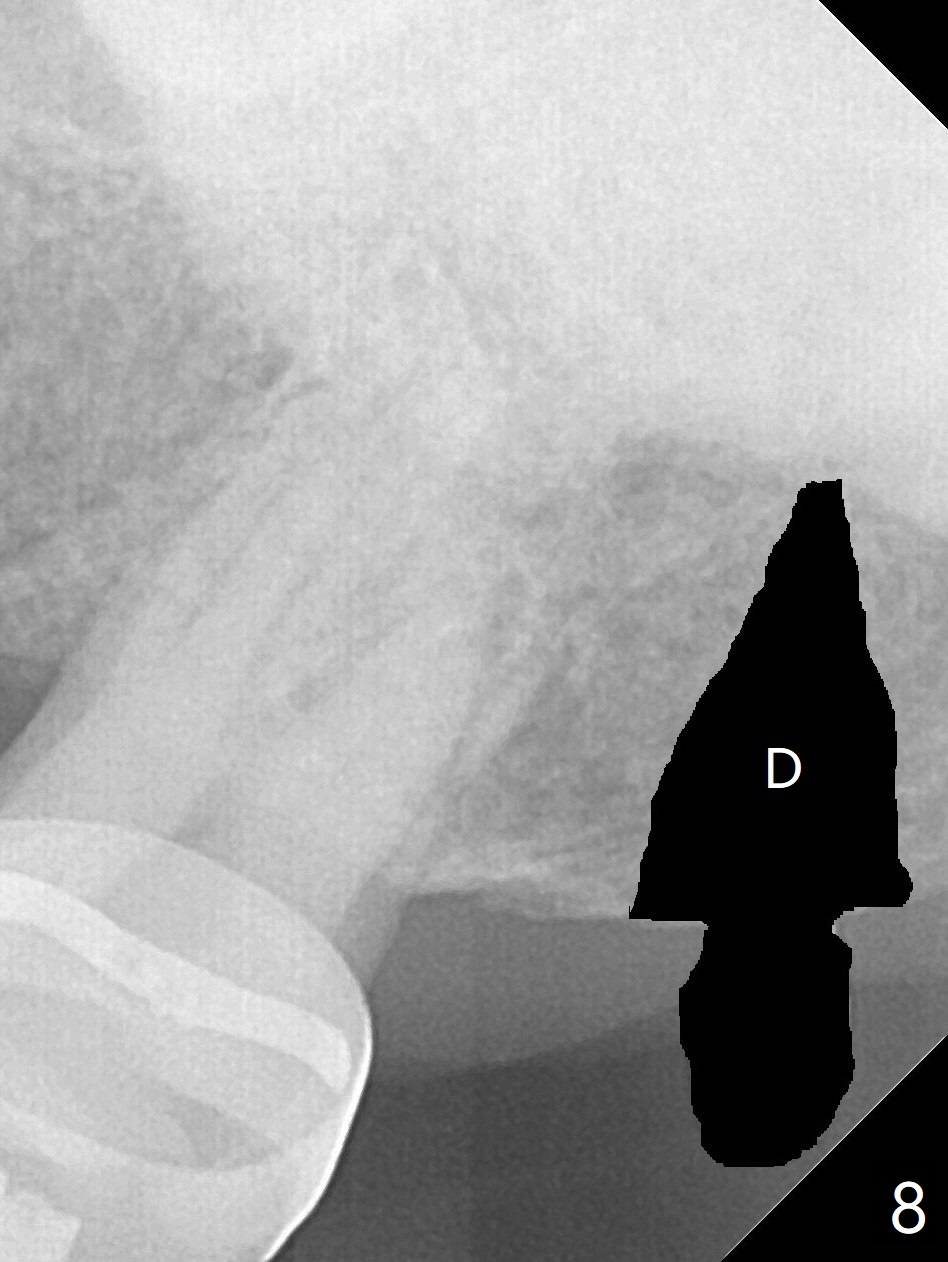

为了在左上6,左下7种植,使用右上3至左上5作为支抗推左上7远中,但是六个月效果不显著(图一),CT显示阻生牙(图一,二:8)没有阻挡。7远中植入1.6x8毫米微型植体,不过接近7根尖(图三),微型植体应该改变角度,而且往远中颊侧移位。最后效果不错(图四),植体马上启用(图五),而且同时取模做左下7导板。在微型植体牵引下,左上7的确往远中移位(图六,与图四对比),但是植体松动,马上植入3x10(2)毫米一段式植体,由于8阻挡,后者没有完全就位,稳定性差,没有启动。几天后也脱落。病人急着完成治疗,因为咀嚼困难。补救方法便是拔除阻生牙9(图七:x),让植体完全就位。切开后发现牙槽嵴处严重骨质吸收缺损(图八:D),离7很近,不适合种植。拔除8后(图九:S(socket)),两处植骨(粘性,图十),覆盖PRF膜,缝合。矫正九个月6空间相当双尖牙(图十二),还想增加2毫米才种植,病人急于完成治疗,所以再次植入微型植体,不同之处是切开,发现7远中颊侧骨质密度低(用探针),因此微型植体在腭侧植入(图十一:P),扭力似乎高,1.6x8毫米植体仿佛植入8牙槽窝(图十二:红虚线)。微型植体牵引一个月,磨牙缺牙间隙大约前磨牙大小,准备在远中(图十三)植入直径小植体(图十四),当后者整合时,用它继续推7。